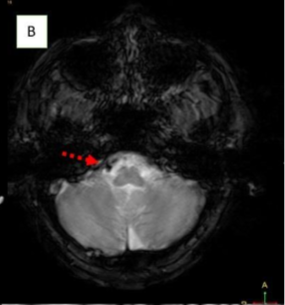

Methods: Two male patients presented with persistent hiccups, nausea, and vomiting. Imaging confirmed lateral medullary infarcts involving the area postrema. Etiological investigations included vascular imaging and thrombophilia workup.

Ischemic Area Postrema Syndrome (APS) is a rare neurological condition characterized by persistent nausea, vomiting, and hiccups resulting from an infarction in the area postrema, a highly vascularized, circumventricular structure in the dorsal medulla. Supplied by small perforating branches of the anterior spinal artery or vertebral artery, this chemoreceptor “vomiting center” lacks a typical blood–brain barrier, making it uniquely vulnerable to ischemic injury. Although ischemic stroke is an infrequent cause of APS, case reports—highlighting dorsal medullary infarcts confirmed on thin-slice diffusion-weighted MRI—demonstrate that small, localized ischemic events can disrupt the area’s function and induce classic APS symptoms.

| MRI Findings | Acute lateral medullary infarct (right area postrema), loss of normal flow void in right vertebral artery and PICA → intraluminal thrombus | Infarct in lateral medullary area, thrombus in right vertebral artery, T2 hyperintensities in bilateral cerebral hemispheres perpendicular to corpus callosum |

Early recognition of APS is crucial for timely diagnosis. In NMOSD, APS can precede MRI findings, warranting early immunotherapy. In contrast to stroke, APS in NMOSD is driven by autoimmune astrocytopathy, where anti-AQP4 IgG binds to astrocytic water channels in the area postrema, triggering complement activation and resulting in astrocyte loss, immunoglobulin/complement deposition, and inflammatory infiltrates. In a stroke, infarction leads to irreversible damage. Ischemic-stroke-induced Area Postrema Syndrome (APS) results from vascular occlusion—typically of perforating branches from the anterior spinal or vertebral arteries—leading to neuronal ischemia, necrosis, and microglial activation within the dorsal medulla, as demonstrated by diffusion-weighted MRI in case reports.